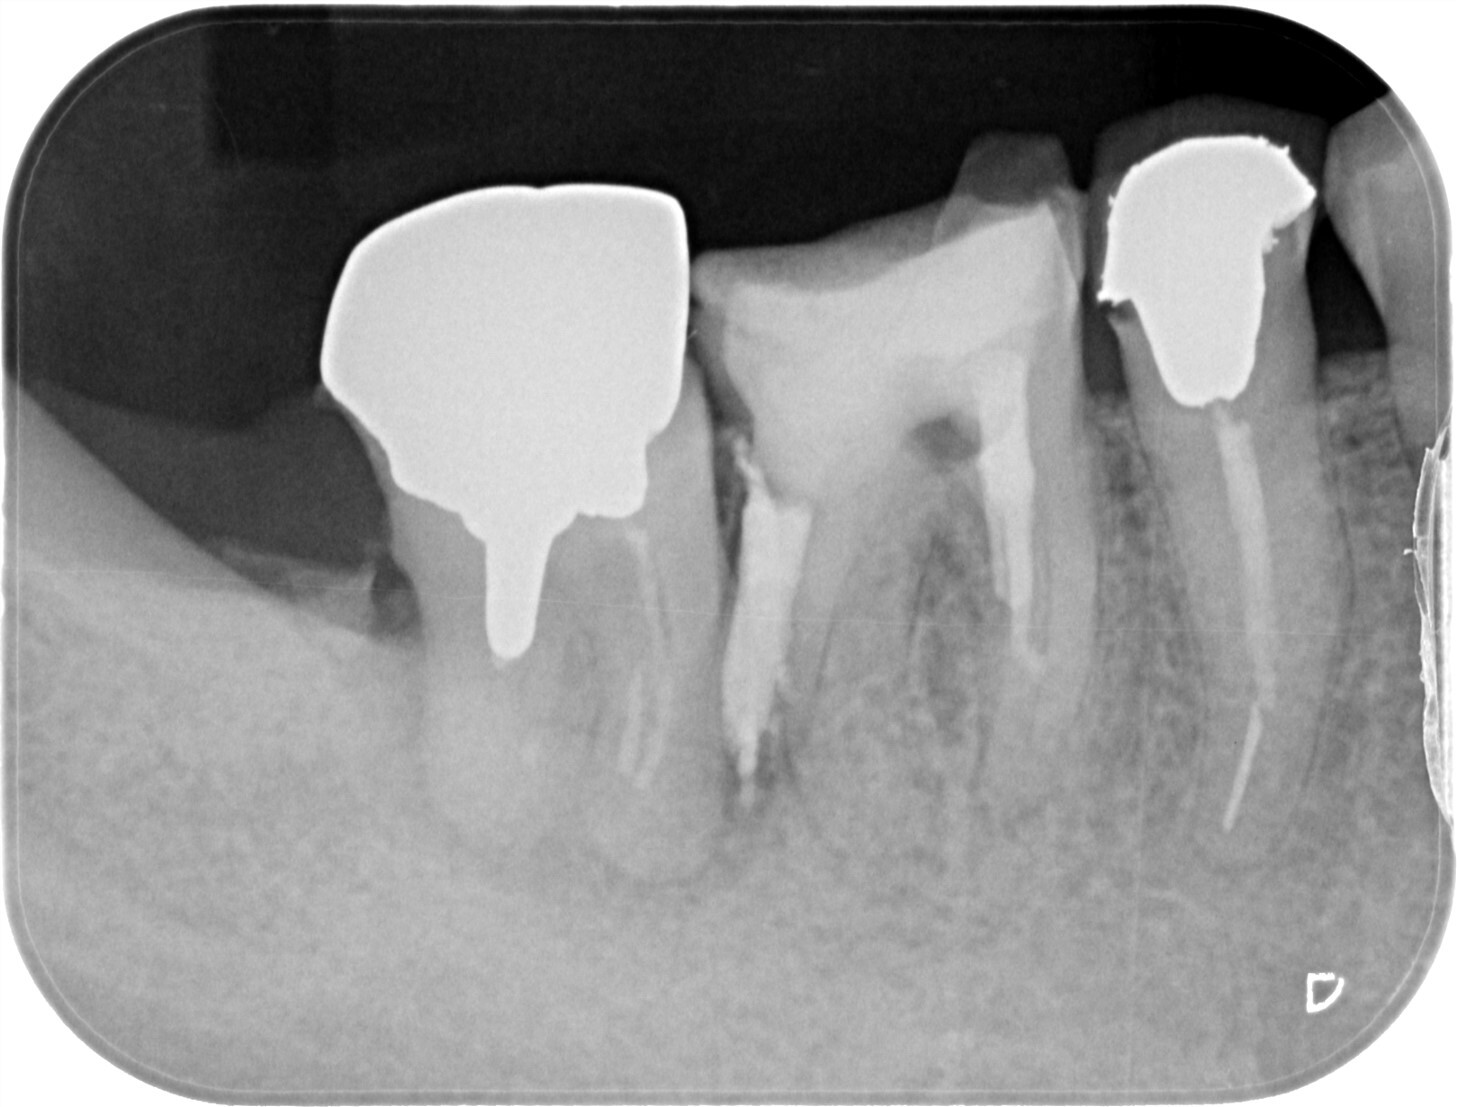

| 主訴 | 過去の治療にて根管充填後、噛むと違和感・痛みが出てきた。一度詰めた薬を撤去してもらったが症状が変わらなかったため来院。 |

| 治療内容 | ラバーダム防湿を行い、マイクロスコープにて根尖部の溢出ガッタパーチャの除去を行いました。 |

CT撮影により根尖部にガッタパーチャの溢出を確認。

拡大視野下にて残存ガッタパーチャを確認しながら過拡大に注意しながら除去。

その後根管充填を行った症例です。ガッタパーチャ除去したことで症状が改善されました。